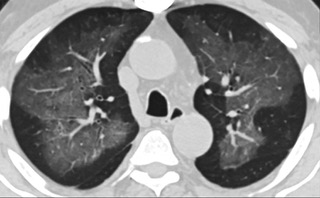

疑点一,电子烟患者的CT影像和临床表现并不具有特异性。所谓美国电子肺炎患者,其实是对没有其他合理诊断证据、吸食电子烟肺炎患者的统称。这些患者在病发前90天内吸食了电子烟,尤其值得注意的是,部分患者的CT影像特征和临床表现与病毒性肺炎患者极其相似。

疑点二,中国科研工作者从60篇研究论文中筛选出142位电子烟肺炎患者的250张影像图片,邀请3位放射科权威专家,对上述全部影像图片、相关病人临床信息以及文献原文进行了仔细全面研究与审查,又有了新的发现。

16位被文献报道为电子烟肺炎的患者被专家判定为“病毒性感染”,即有可能是新冠肺炎的“疑诊患者”,其中更有5位临床症状和治疗情况相对完整的患者被判定为“中度可疑”。因此在2019年美国报道的电子烟肺炎中存在病毒性感染的病例,而且不排除美国电子烟肺炎中存在新冠肺炎的可能性。